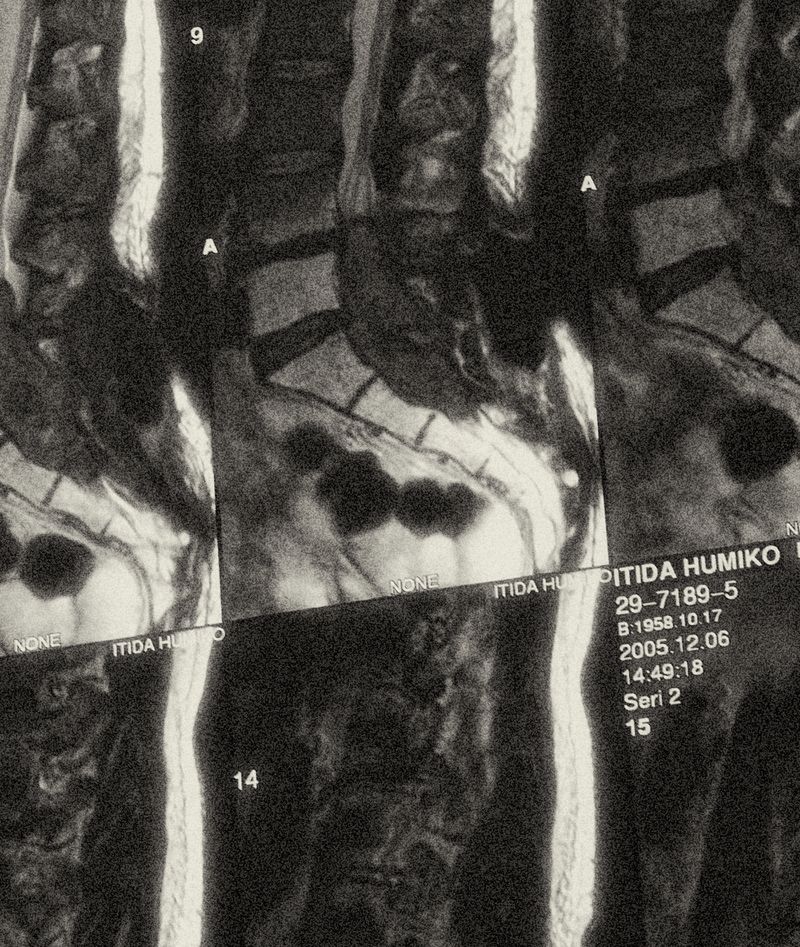

My mother's cause of death was lung cancer. She was 47. After a valiant two-year battle, it spread all over her body despite all efforts.

© Sayuri Ichida - Image from the Fumiko photography project